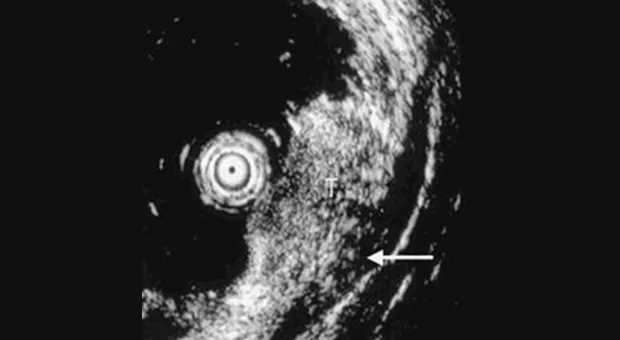

Правильное установление стадии развития опухоли необходимо для выбора приемлемого метода лечения. С развитием эндоскопического УЗИ увеличилась его точность определения глубины инвазии опухоли (Т). Kelly с соавторами [2] объединил результаты 27 статей посвященных эндоскопическому УЗИ в определении стадии рака пищевода и желудка по TNM и пришел к выводу, что эндоскопическое УЗИ имеет высокую степень точности в установлении стадии заболевания.

Caletti с коллегами [3] сообщают, что точность эндоскопического УЗИ в установлении стадии достигает 80 % по Т и около 77 % по N. В последнем опубликованном обзоре [4] точность установления стадии рака желудка варьировало от 67 % до 92 %. Согласно данных представленных Murata с коллегами [5] чувствительность и специфичность определения инвазии с мышечную пластинку слизистой оболочки при использовании зонда с частотой 20-MHz была 97 % и 87 % соответственно. В дополнение к этому, по данным крупнейшего Американского исследования по резекции слизистой [6], наблюдается высокий уровень совпадения между данными полученными при высокочастотном ультразвуковом сканировании и морфологическими находками (96 %).

Sampliner коллегами [50] использовали мультиполярную электрокоагуляцию у 10 пациентов для лечения половины окружности занятой пищеводом Баррета. На момент публикации их данных у всех 10 пациентов наблюдалась полная элиминация пищевода Баррета на участках подвергшихся лечению (в среднем 2,5 сеанса). Sharma коллегами [51] пролечил мультиполярной коагуляцией 11 пациентов, причем потребовалось в среднем 9,5 сеансов для достижения полной реверсии слизистой пищевода Баррета. При средних сроках наблюдения в 24 месяца у 3 из 11 имелась кишечная метаплазия под вновь образовавшимся плоским эпителием. Наиболее крупное и новое мультицентровое исследование было проведено Sampliner коллегами [52]. В нем 72 пациента были пролечены с использованием мультиполярной коагуляции. У 8 пациентов не было выявлено пищевода Баррета, еще у 8 реверсия не была достигнута через 6 сеансов терапии. У 54 (78 %) из оставшихся 58 достигнута полная реверсия пищевода Баррета после, в среднем, 3,5 сеансов. Существуют свидетельства указывающие, что уменьшение толщины стенки пищевода при эндоскопическом УЗИ у пациентов после мультиполярной электрокоагуляции ассоциированно с гистологическим отсутствием кишечной метаплазии [53].